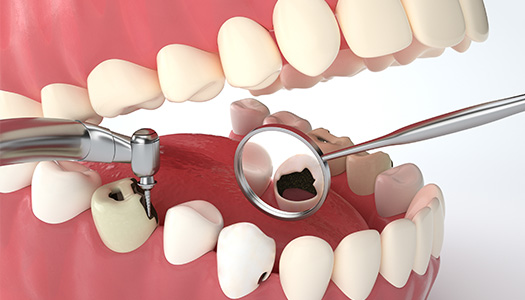

口腔科诊疗项目齐全,技术特色鲜明,系统性地开展以下专业诊疗服务:

牙体牙髓疾病

专业开展各类龋病(蛀牙)的精密充填治疗、现代根管治疗(显微根管治疗)及牙体缺损的诊断与修复。